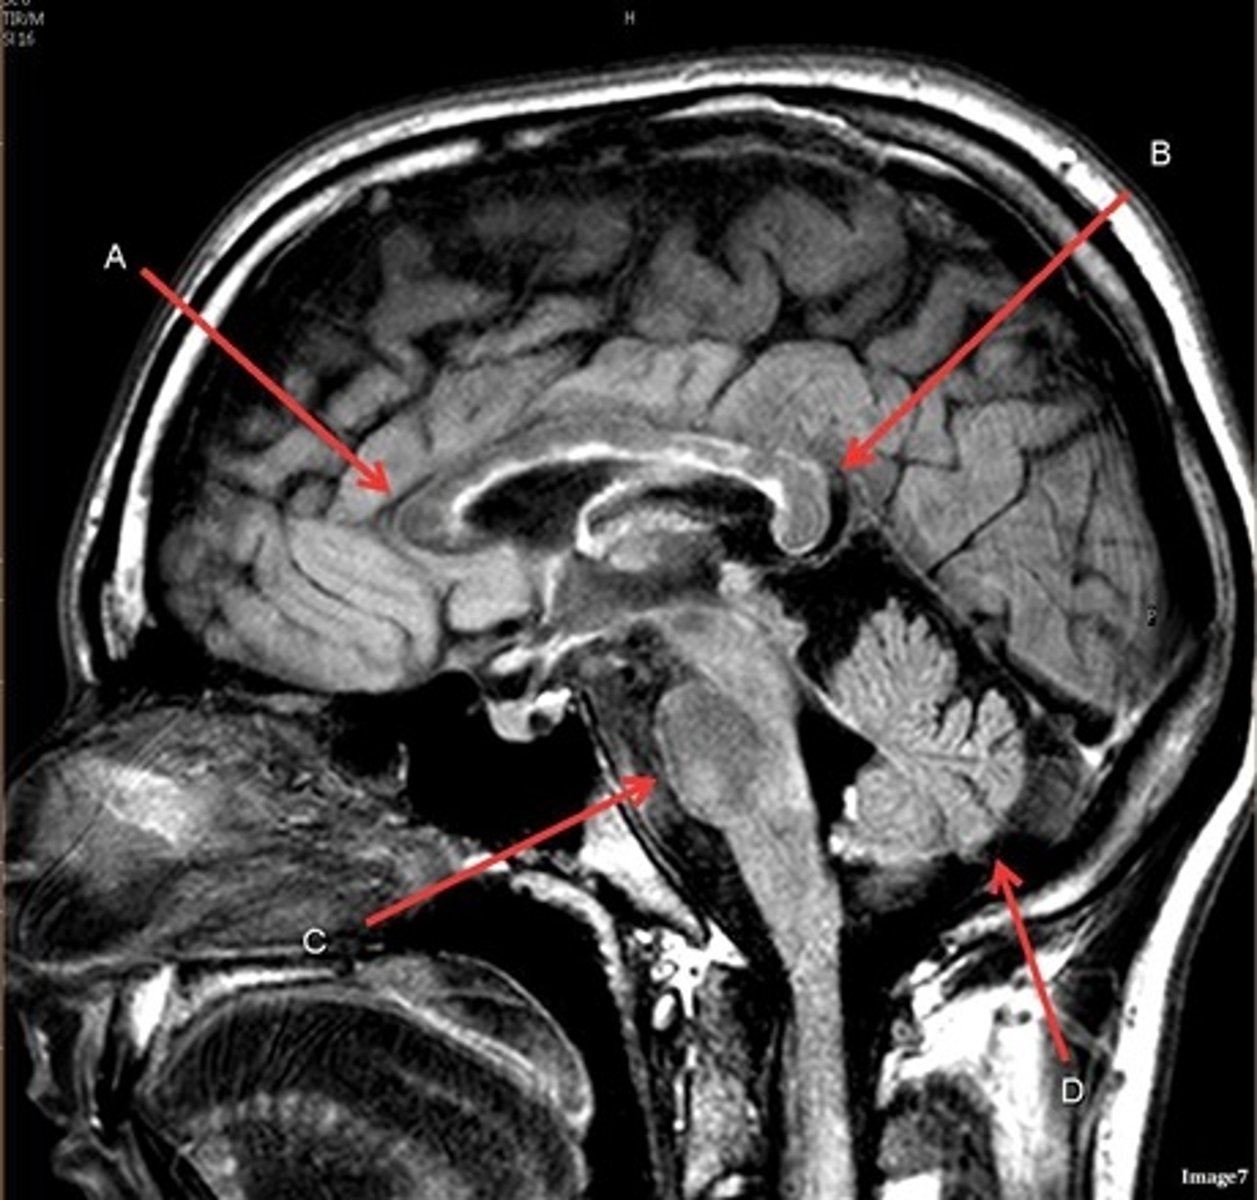

What type of sequence?

T2 FLAIR; Sagittal

A FLAIR (Fluid Attenuated Inversion Recovery) sequence is utilized to suppress signal from cerebrospinal fluid (CSF).

A- region

Genu of Corpus Callosum

B- region

Splenium of Corpus Callosum

C

pons

D

cerebellum